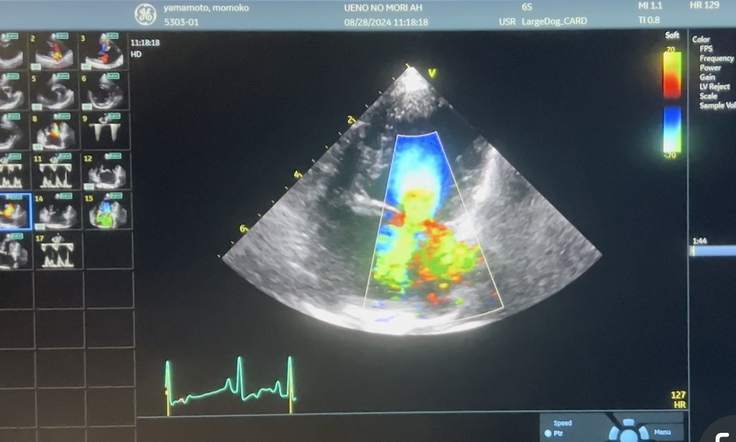

・こちらはももこのエコー

ご覧の通り緑の部分がかなり多いです。